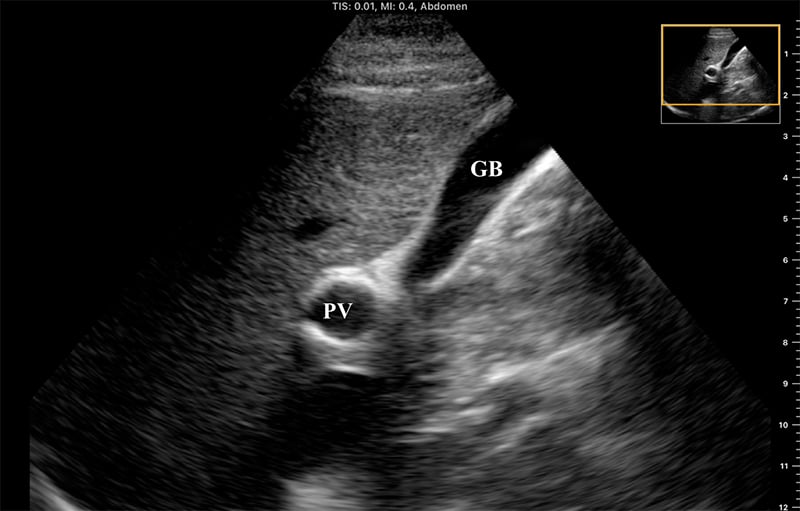

- The portal vein may also be located in short axis by tracing the gallbladder down its long axis to the neck, forming the “exclamation point”

Figure 9. “Exclamation point” revealing the gallbladder (GB) in long axis with the bright-walled portal vein (PV) in short axis.

- The larger, bright-walled portal vein will often be seen with the two smaller structures of the portal triad in the same cross section, a hepatic arterial branch and common bile duct.